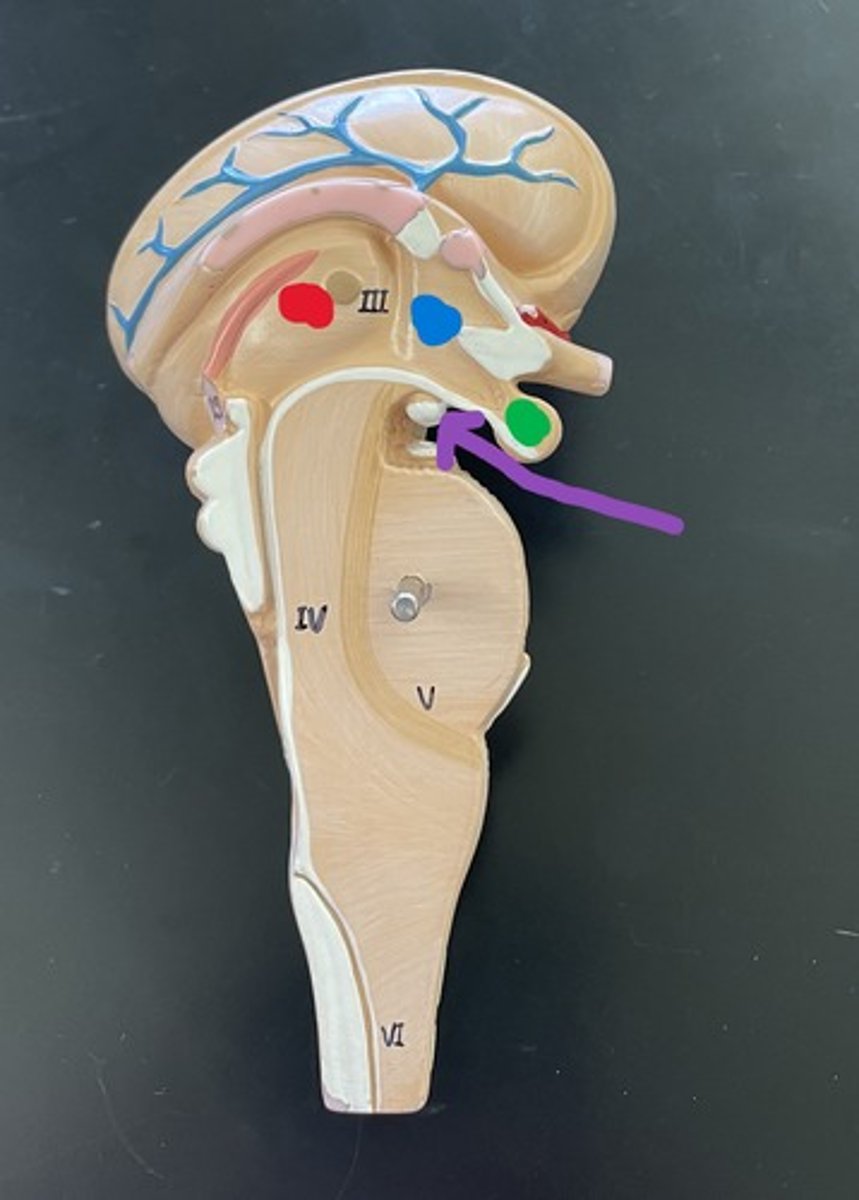

Pineal gland

25

Hypothalamus

blue

Pituitary gland

Anterior pituitary gland

Anterior pituitary gland

Posterior pituitary gland

Posterior pituitary gland